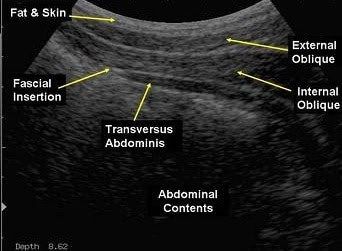

At Palmer Physical Therapy for Women, we are proud to offer physical therapy sessions enhanced by real-time ultrasound imaging. Real-time ultrasound allows us to visualize the function of your core and pelvic floor muscles as they contract and relax. Using safe, noninvasive sound waves, this technology produces a continuous, live image of your internal body structures. This enables precise assessment, immediate feedback, and more targeted treatment to help you achieve optimal results.